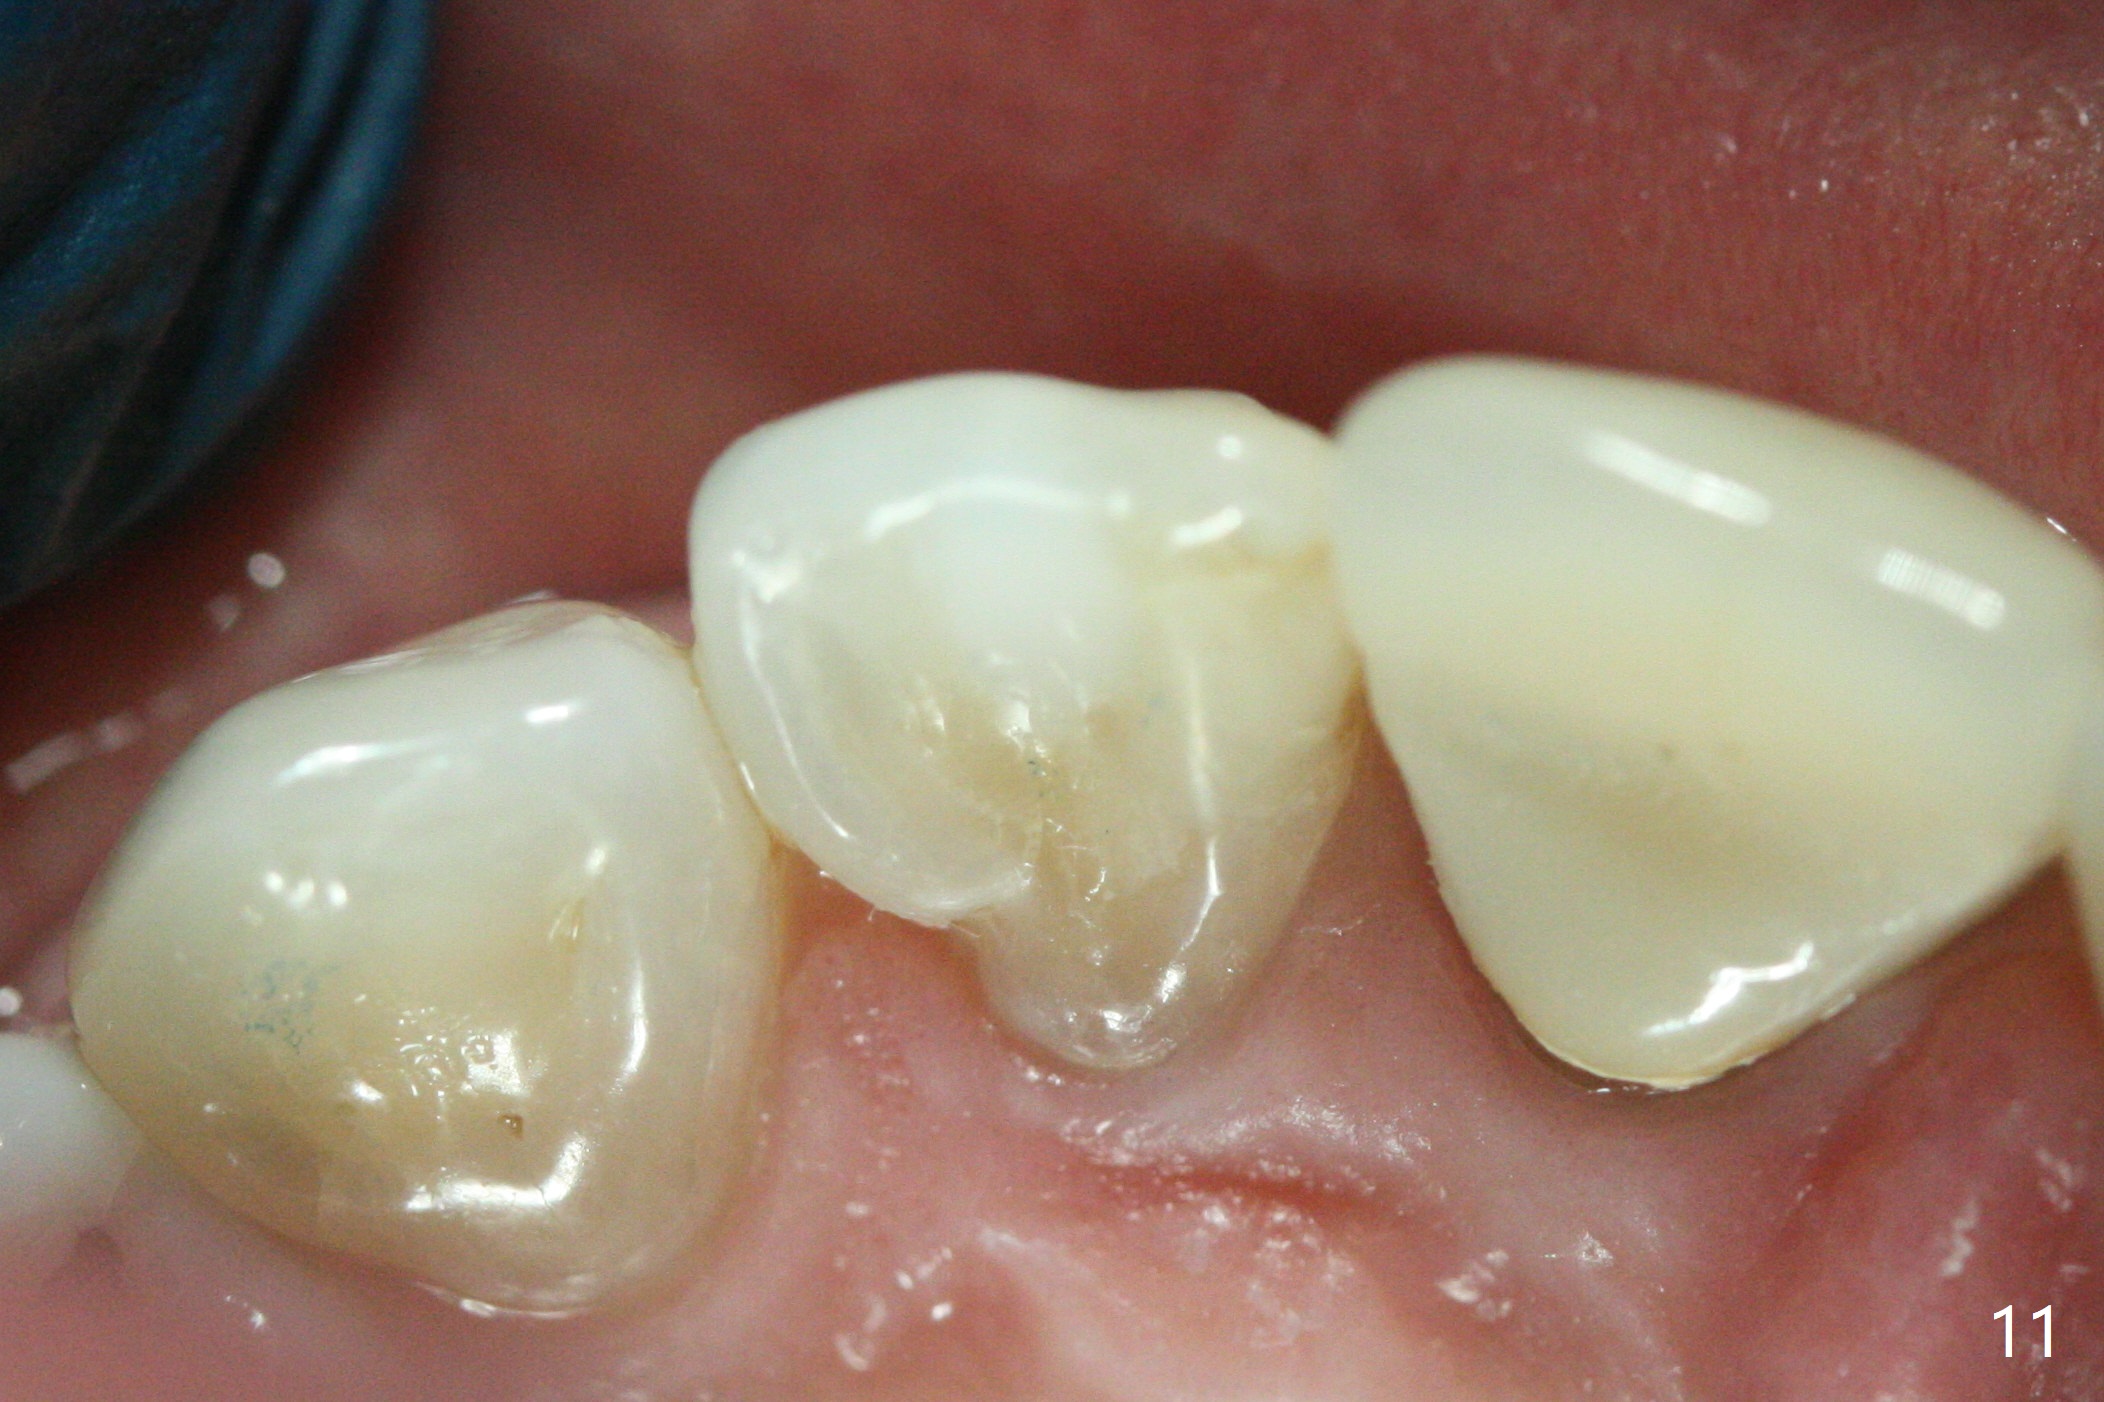

A 46-year-old woman requests a crown for the discolored tooth #7 (Fig.1,2) with mesiolingual composite (Fig.3 C) and periapical radiolucency (*). After RCT (Fig.4,5) with sodium hypochlorite, the tooth #7 is whiter than the ML composite (Fig.6,7). The patient returns 1 day post RCT for in house internal and external bleaching (Fig.8) with 35% hydrogen peroxide gel closed in the canal when she leaves. Three weeks later, the lateral incisor has the shade as the neighboring natural teeth (Fig.9,10). After the lightest shade composite placed in the canal and the access hole (Fig.11), the lateral looks better than the central with a crown and cervical discoloration (Fig.12).